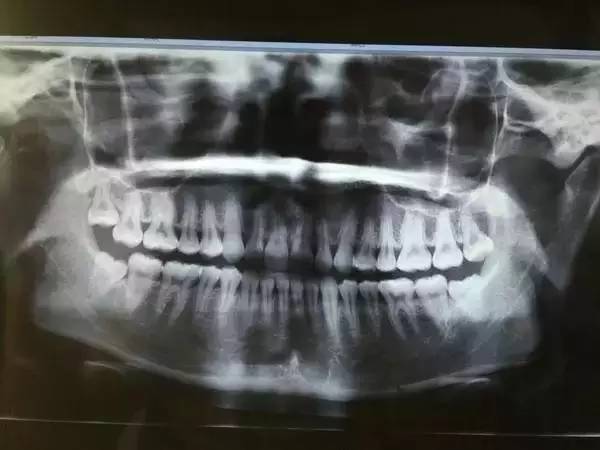

2、侵略鄰牙

一般患者不自知,而由牙醫(yī)以X光確診得知。一般智齒萌生的空間缺乏,而會(huì)倒在第二大臼齒上,因而形成第二大臼齒清洗不易,乃至是牙齒部分吸收的表象,形成患者不舒服或牙疼。

6、阻生齒

一般這是最討厭的一種,牙醫(yī)會(huì)覺得很難搞定,但患者卻不一定有感受,因而忽略了。這一種類型的牙齒,一般埋在齒槽骨的里邊,假如會(huì)痛,或是確診會(huì)有病灶發(fā)作的時(shí)分,就需求拔除了。